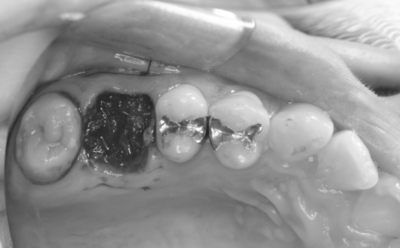

初診時口腔内写真

初診時パノラマX線写真と口腔内写真。

右上6に腫脹と排膿がみられた。